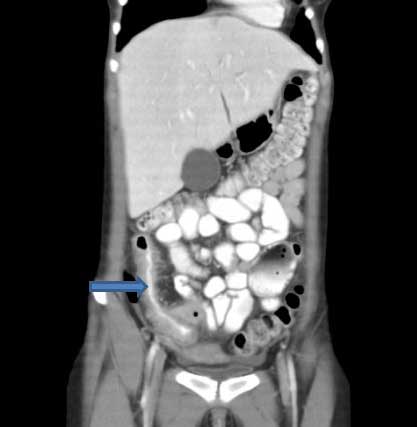

Abdominal CT scan with oral and intravenous contrast to look for small-bowel lymphoma, Crohn's disease, or pancreatic abnormalities.[Figure caption and citation for the preceding image starts]: CT scan demonstrating thickening of the terminal ileum in a patient with Crohn's disease exacerbationCourtesy of Drs Wissam Bleibel, Bishal Mainali, Chandrashekhar Thukral, and Mark A. Peppercorn; used with permission [Citation ends].

[Figure caption and citation for the preceding image starts]: CT scan demonstrating thickening of the terminal ileum in a patient with Crohn's disease exacerbationCourtesy of Drs Wissam Bleibel, Bishal Mainali, Chandrashekhar Thukral, and Mark A. Peppercorn; used with permission [Citation ends].